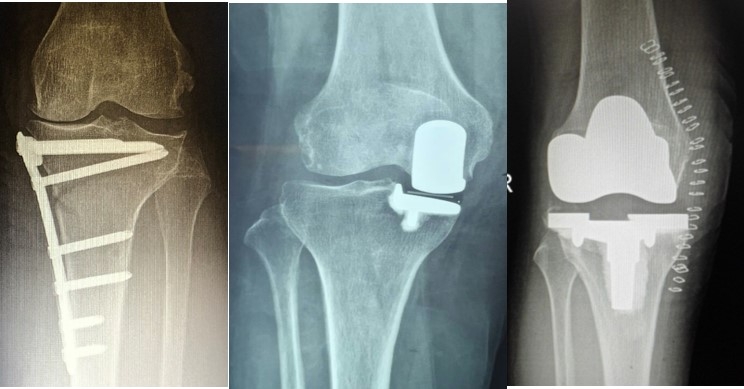

手术治疗包括关节镜下髓芯减压术、自体软骨移植术、HTO、关节置换术(UKA、TKA)。

(2)Koshino Ⅱ期 SONK

优先选择保守治疗方案,或在保守治疗方案的基础上配合行钻孔减压术,由于Koshino Ⅱ期的关节软骨仍相对完整,借助间充质细胞的重建作用及钻孔后骨内压力的降低,在该期仍可取得满意的疗效。

(3)Koshino Ⅲ期 SONK

需在考虑5个因素的基础上,同时兼顾考虑年龄、性别和活跃程度,分别选择用膝关节镜+自体骨软骨移植术(当患者下肢力线内翻<3°时)膝关节镜+HTO术+微骨折术、膝关节镜+HTO+坏死区病灶刮除+自体植骨术或单髁置换术。

病例1:女,61岁,右膝关节诊断为Koshino Ⅲ期SONK,行右膝内侧单髁手术治疗。

(4)Koshino Ⅳ期SONK

由于存在继发退行性改变,一般不建议单纯行膝关节镜+自体骨软骨移植术。需在考虑5个因素的基础上兼顾患者年龄、性别和活跃程度,分别选择膝关节镜+HTO术+微骨折术、膝关节镜+HTO+坏死区病灶刮除+自体植骨术或单髁置换术。对于合并症状性髌股关节炎、外翻畸形、坏死区范围大影响单髁假体稳定性等的Koshino Ⅳ期膝关节股骨内侧髁SONK,采用全膝关节置换术。

病例2:女,81岁,行内侧单髁手术治疗,术后恢复良好。